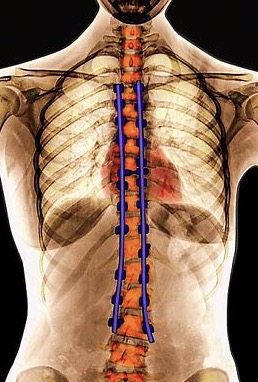

脊柱侧弯术后要注意的问题以及的康复重点

术后康复训练要点:1、肺部功能训练:正确的咳嗽、咳痰;吹气球;向没有装满水的瓶子里吹气。2、胃肠功能训练:患者术后1-3天会出现腹胀,这是正常的,建议以流质饮食为主,粥或蛋白粉等,可以按摩腹部,也可以做自主收复提肛的运动,促进肠道提起排出 3、四肢功能训练。.....

布骨始终按照脊柱侧弯矫正和康复治疗SOSORT的指南进行脊柱侧弯矫正治疗

布骨始终脊柱侧弯矫正和康复治疗SOSORT的指南进行脊柱侧弯矫正治疗,包括体态纠正、手法治疗、物理因子治疗、脊柱侧弯术前术后康复、运动医学、矫形学和医生或物理治疗师的个人临床实践。我们绝对不提倡“观察和等待”的方法 布骨严格按照脊柱侧弯矫正和康复治疗SOSORT的指南进行脊柱侧弯矫正治疗,不去做无.....